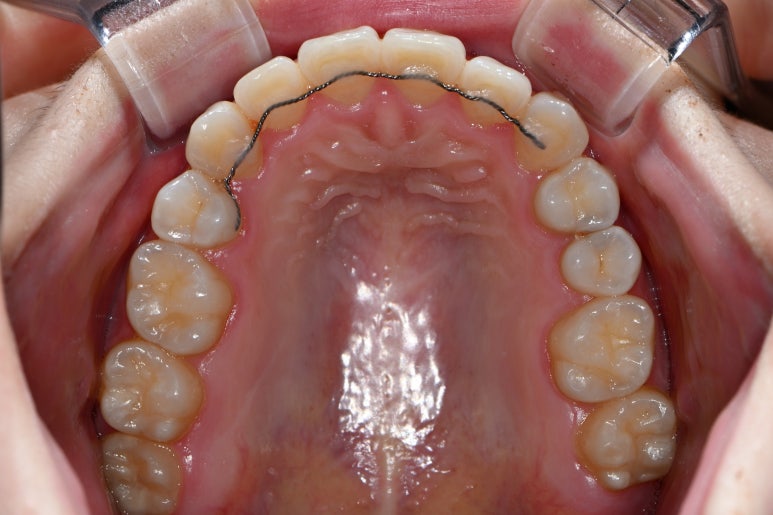

이렇게 입천장을 바라보는 샷을 저희는 교합면 뷰 라고 부릅니다.

잘 보면 충치가 어딨는지 아실 수 있을거에요~~ 잘 구별하실 수 있으시겠어요..?

알아보기 쉽게 충치가 있는 곳만 떼서 표시를 해봤습니다.

옆면 충치가 생기셔서 검게 멍든 것처럼 보이는 치아... 양쪽이 동시에 썩었더라구요...